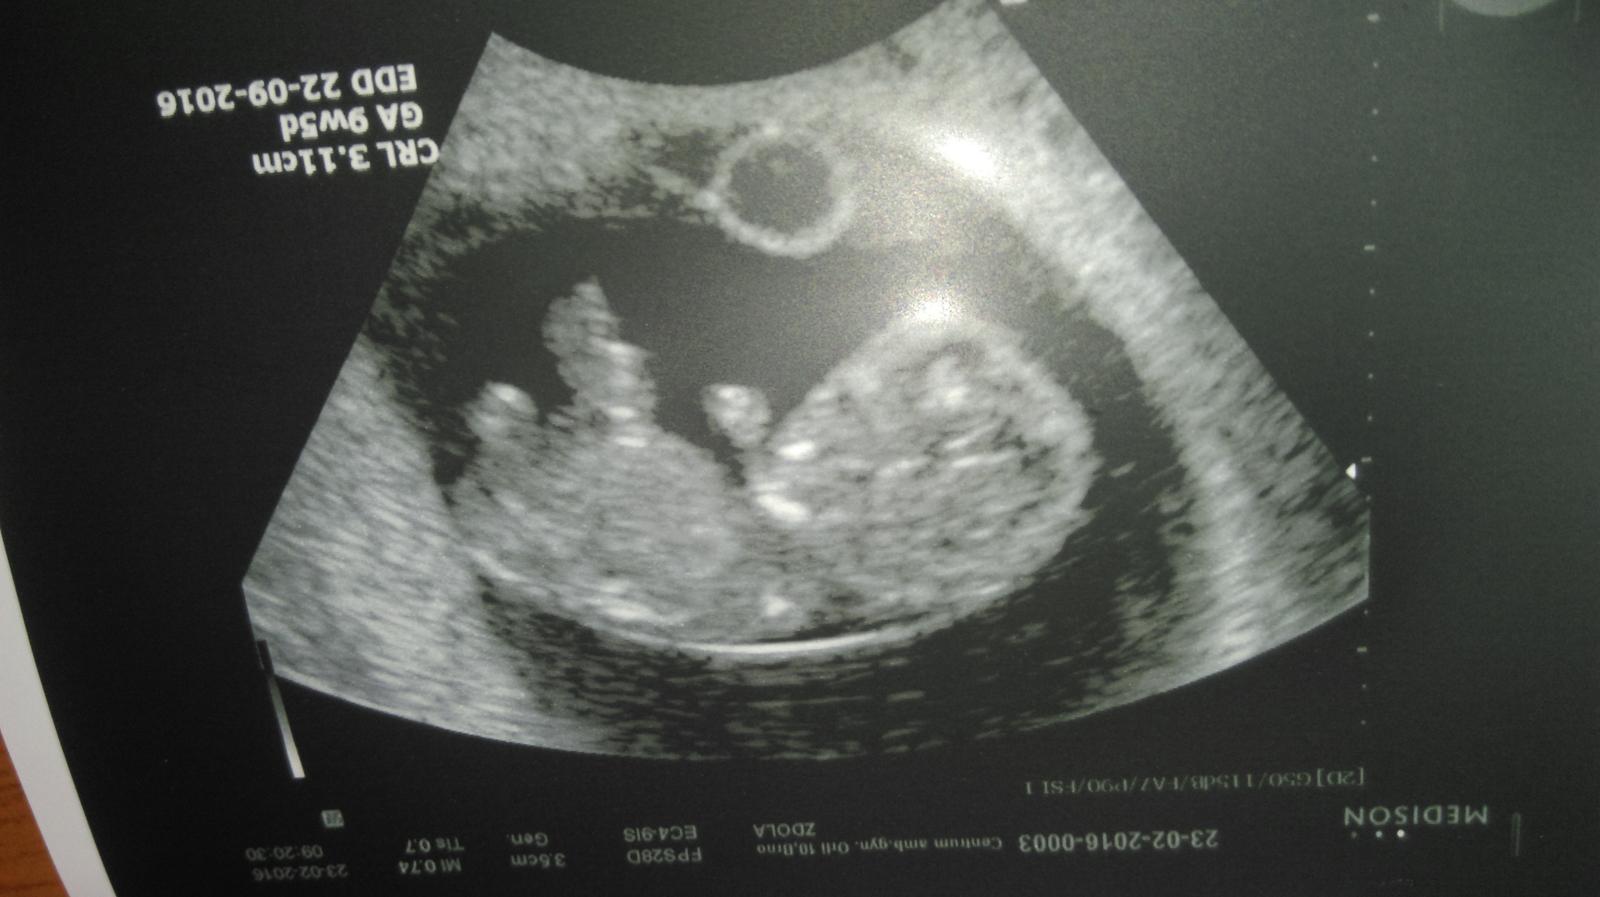

@hermanek1985 ahojky 🙂 zapomněla jsem už tady přispívat..aby třeba nebyl někdo smutný, že se nedaří... Já už jsem v 11.týdnu, nezvracím ani mě nic nebolí, tak jsem ráda. A už mám první fotečku z ultrazvuku 🙂 a jak se vede? Kde jste byli na dovči?